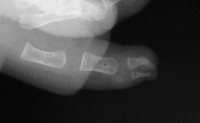

| Case 1. Wassell IV duplication of the proximal and distal phalanges, with characteristic deviation of the thumbs away from each other at the MCP and toward each other at the IP joints. This was corrected by metacarpal head narrowing, opposing closing wedge osteotomies of the metacarpal and proximal phalanx and collateral ligament reconstruction using parts from the deleted digit. |